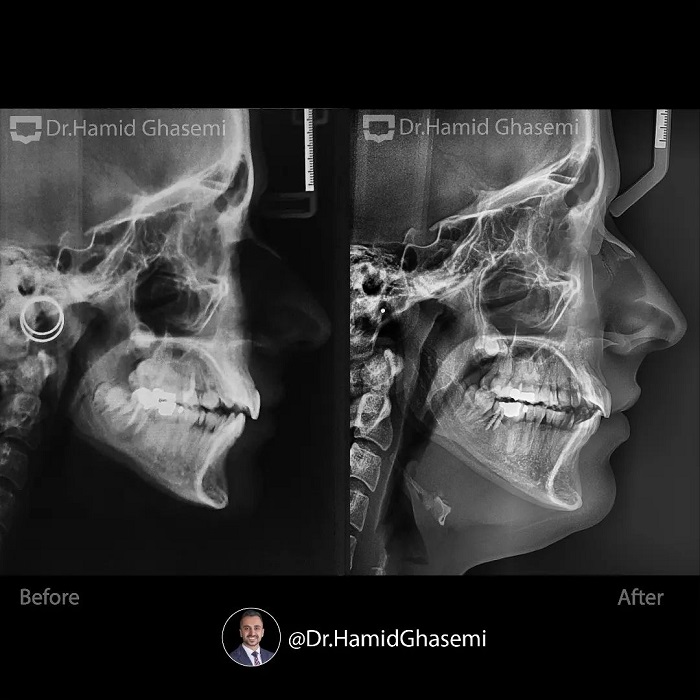

این کیس یک نمونه خوب از استفاده دو تکنیک متفاوت جهت دیستالیزیشن(عقب بردن) در فک بالا و پایین هست. مشکلات کیس عبارتند از: پروتروژن دندانی هر دوفک، کراودینگ شدید دندانی، اپن بایت قدامی در دختر ۱۶ ساله. در فک بالا دیستالیزیشن با کشیدن دندانهای پرمولر دوم (استفاده از تکنیک اسلایدینگ و لوپ مکانیک) انجام شد ولی در فک پایین توتال آرچ دیستالیزیشن(با استفاده از اسکروهای باکال شلف مندیبل) انجام شد به این دلیل که دندانهای آسیاب دوم غیر قابل نگهداری با پروگنوز بسیار ضعیف بودند و در روند درمان دندانهای عقل فک پایین جایگزین دندانهای آسیاب دوم شدند.

This case is a very good example of 2 different biomechanics in upper and lower arch in order to perform distalization. A case is a typical bimaxillary dentoalveolar protrusion with severe crowding and anterior openbite in 16 years old girl. In upper arch i decided to extract upper 2nd premolars in order to perform distalization (using conventional sliding and closing loop mechanics) but in lower arch the best choice was to perform total arch distalization(using buccal shelf screws) since lower 2nd molars were hopeless with very poor prognosis and then lower 3rd molars were substituted accordingly.